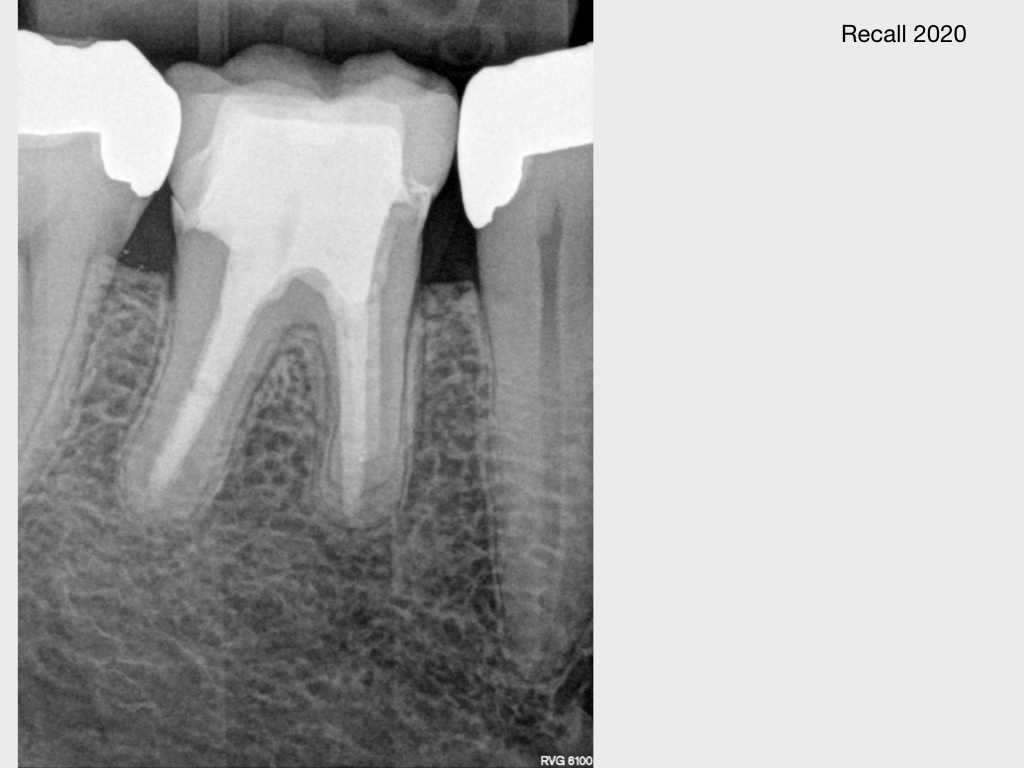

Kurz berichtet – Z.n. WSR